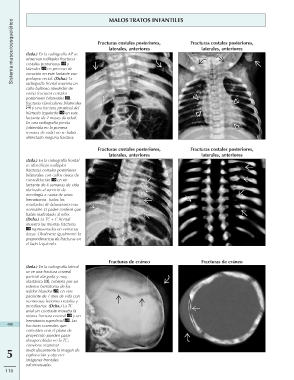

Sistema musculoesquelético MALOS TRATOS INFANTILES

(Izda.) En la radiografía AP se Fracturas costales posteriores, Fracturas costales posteriores,

observan múltiples fracturas laterales, anteriores laterales, anteriores

costales posteriores y

laterales en proceso de Fracturas costales posteriores, Fracturas costales posteriores,

curación en este lactante con laterales, anteriores laterales, anteriores

prolapso rectal. (Dcha.) La

radiografía frontal muestra un Fracturas de cráneo Fracturas de cráneo

callo bulboso alrededor de

varias fracturas costales

posteriores bilaterales ,

fracturas claviculares bilaterales

y una fractura proximal del

húmedo izquierdo en este

lactante de 2 meses de edad.

En una radiografía previa

(obtenida en la primera

semana de vida) no se había

detectado ninguna fractura.

(Izda.) En la radiografía frontal

se identifican múltiples

fracturas costales posteriores

bilaterales con callos óseos de

consolidación en un

lactante de 6 semanas de vida

derivado al servicio de

oncología a causa de unos

hematomas. Todos los

resultados de laboratorio eran

normales. El padre confesó que

había maltratado al niño.

(Dcha.) La TC + C frontal

muestra las mismas fracturas

representadas en ventanas

óseas. Obsérvese igualmente la

preponderancia de fracturas en

el lado izquierdo.

(Izda.) En la radiografía lateral

se ve una fractura craneal

parietal alargada y muy

diastásica , cubierta por un

extenso hematoma de los

tejidos blandos , en este

paciente de 1 mes de vida con

numerosas lesiones costales y

metafisarias. (Dcha.) La TC

axial sin contraste muestra la

misma fractura craneal y un

hematoma superficial . Las

490 fracturas craneales que

coinciden con el plano de

proyección pueden pasar

desapercibidas en la TC;

conviene examinar

5 meticulosamente la imagen de

exploración y obtener

imágenes frontales

reformateadas.